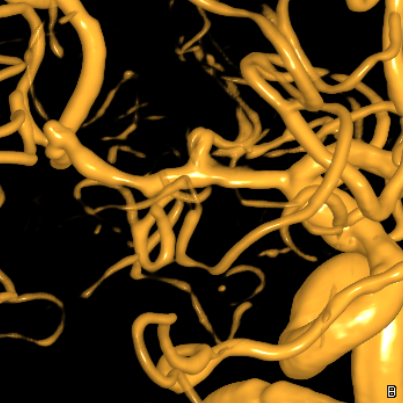

右侧MCA长节段血管变细狭长

长节段MCA血管狭长变细,尤以近端为重

血管不错

重建的形态

血管形态